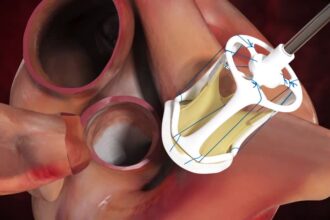

تعتمد العلاجات على نوع المرض وشدته، وتشمل الأدوية للتحكم في الأعراض أو تحسين وظائف القلب، والقسطرة لتوسيع الصمام الضيق، أو الجراحة لإصلاح أو استبدال الصمام المتضرر.

جراحه اصلاح الصمام الميترالي

تعتبر جراحه اصلاح الصمام الميترالي هي الحل الامثل…

تتعدد الأمراض والمشاكل التي يمكن أن تصيب القلب،…